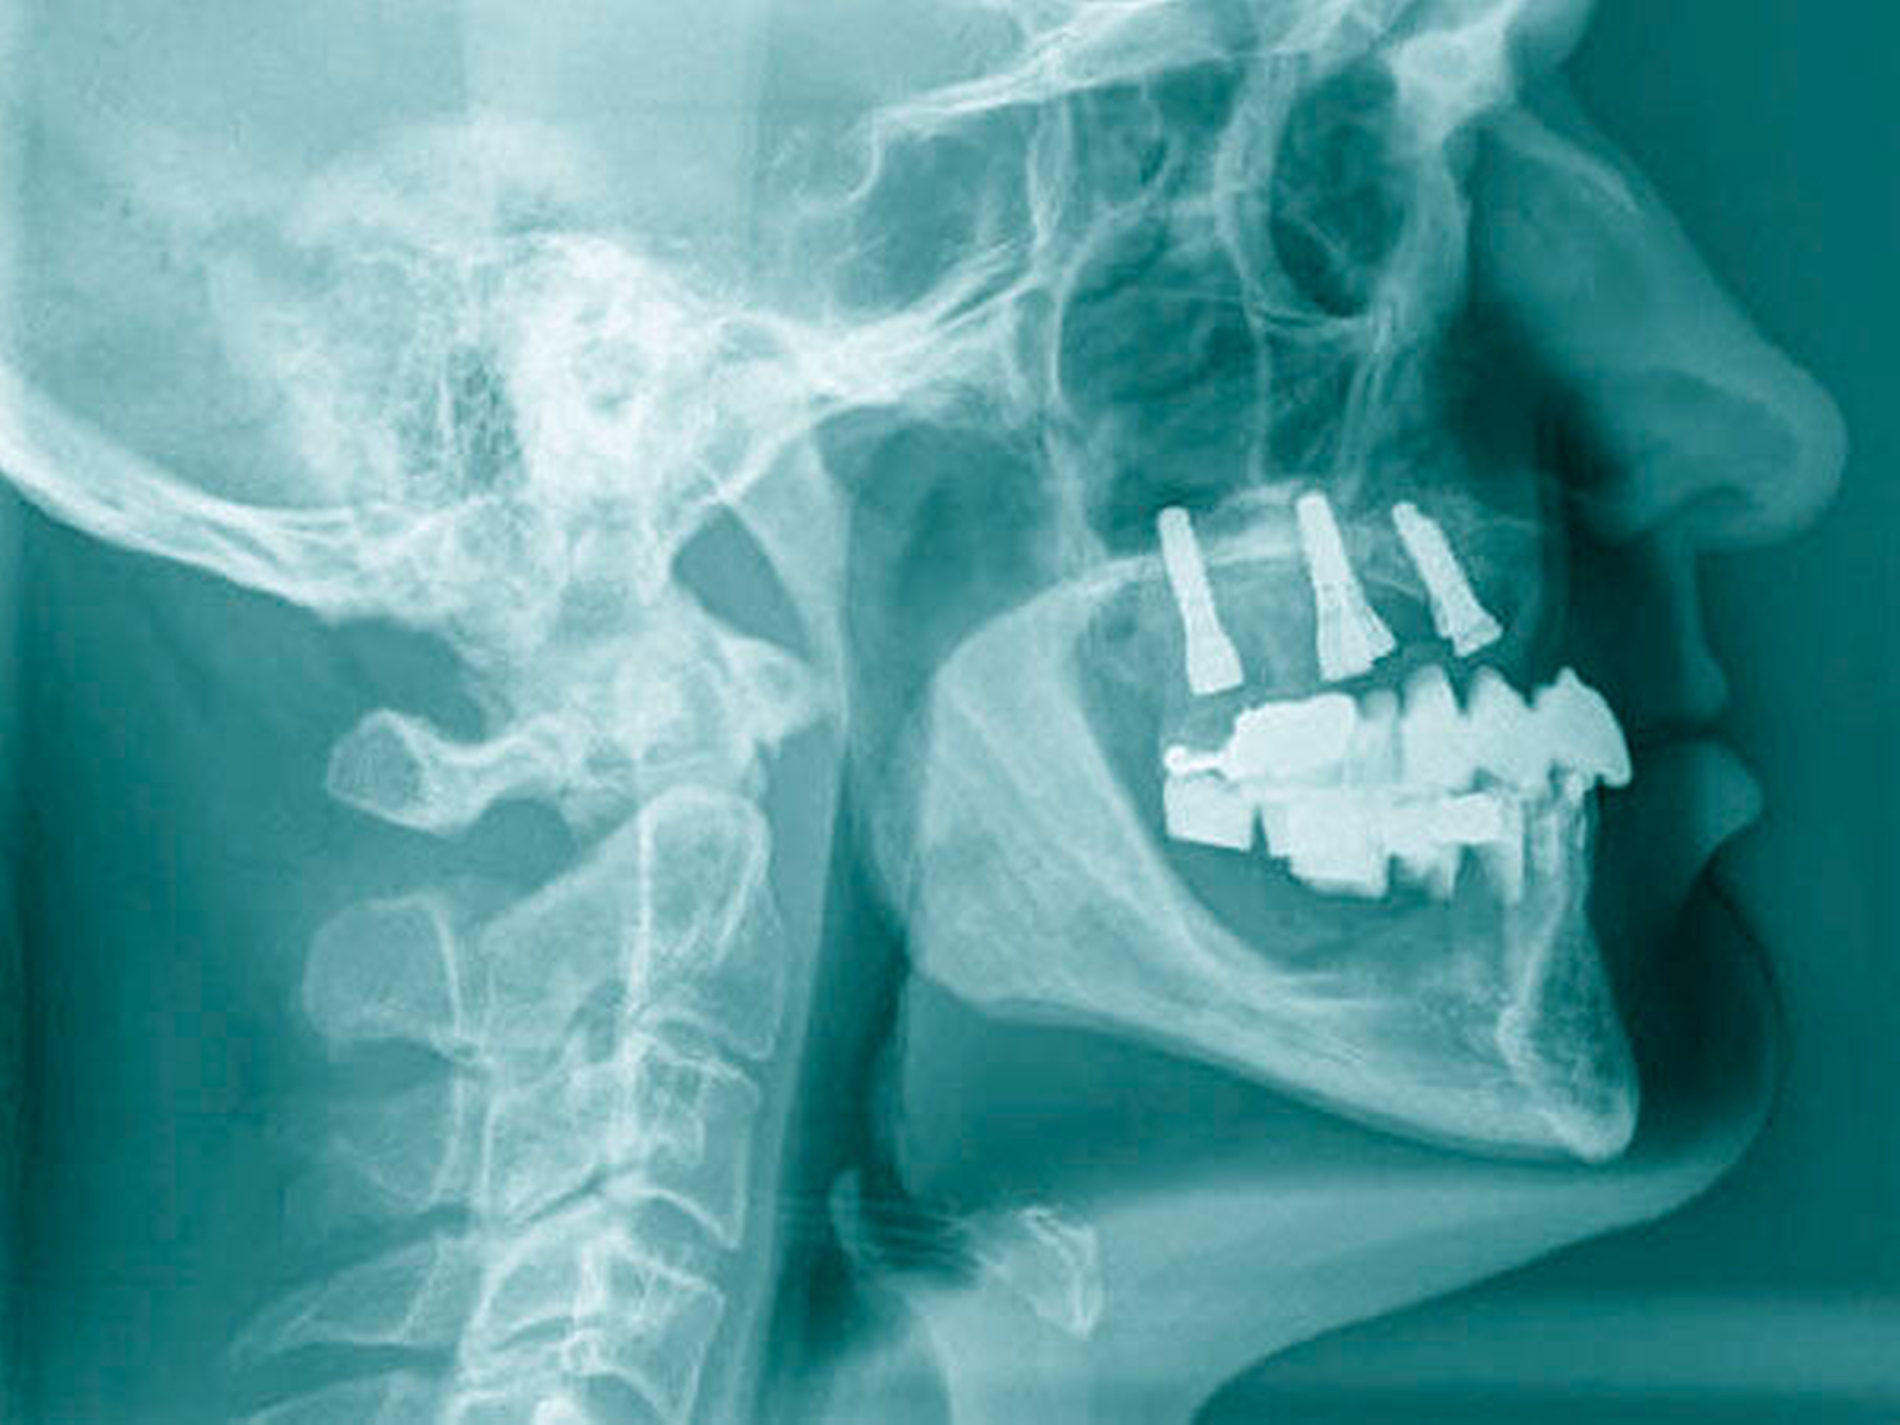

Die klinische Situation zeigte einen atrophierten, teilbezahnten Oberkiefer (herausnehmbarer, nicht implantatgetragener Zahnersatz) sowie einen teilbezahnten Unterkiefer (herausnehmbarer, mit Klammern verankerter Interimszahnersatz) (Abbildung 1). Vor allem fiel der prothetisch eingestellte Kopfbiss im Frontzahnbereich mit ausgeprägter negativer sagittaler Stufe bei einer Rücklage des Oberkiefers von 0,8 cm auf. In der alio loco angefertigten prä-implantologischen Röntgendiagnostik mittels Panoramaschichtaufnahme war dies nicht zu erkennen. Aufgrund des klinischen Bildes eines defizitären Mittelgesichtsprofils erfolgte eine kephalometrische Analyse. Hier bestätigten die ermittelten Werte eine maxilläre Retrognathie (Angle-Klasse III; Abbildung 2).

Insgesamt lag somit eine prothetisch schwierig zu versorgende Situation vor, weshalb nach ausführlicher interdisziplinärer Besprechung gemeinsam mit dem Patienten die Entscheidung zugunsten einer Le-Fort-I-Osteotomie zur Behebung der sklelettalen Fehlstellung und zur Verbesserung des Gesichtsprofils getroffen wurde. Simultan konnten die in situ befindlichen Implantate für den provisorischen Zahnersatz im Sinne eines Operationssplints genutzt werden. Nach der Modelloperation am Artikulator und der Anfertigung sowie der Eingliederung eines individuellen CAD/CAM-gefrästen temporären Zahnersatzes (Poly-Temp®, ceramill®; Amann Girrbach GmbH, Pforzheim, Deutschland) im Oberkiefer (Abbildung 3) erfolgte die maxilläre Umstellungsosteotomie mittels Osteotomie in Le-Fort-I-Ebene. Die temporäre Restauration sicherte intra- und postoperativ die Kieferrelation und Okklusion (Abbildung 4).

Nach unauffälliger Heilung ohne Komplikationen und Korrektur der Kieferrelation (Abbildung 5) konnte die definitive Versorgung (CARES®; Straumann, Basel, Schweiz; Sinfony®, 3M ESPE, Seefeld, Deutschland) drei Monate später eingegliedert werden (Abbildung 6). Im Rahmen der Nachsorgeuntersuchungen (Follow-up aktuell: 2,5 Jahre) zeigten sich stabile Okklusionsverhältnisse bei reizlosem Lokalbefund.